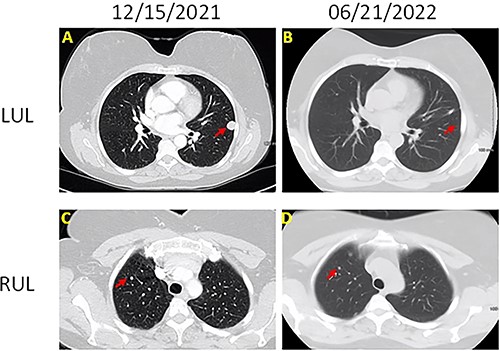

Left upper lobe wedge resection was performed. On gross examination, the nodule was tan-white, well-circumscribed, firm, homogeneous, measuring 1.5 × 1.3 × 0.7 cm, abutting the pleura. Microscopically, this tumor was composed of bland epithelioid and spindle cells with moderate amount of cytoplasm, whorl formation and occasional pseudo-nuclear inclusions (Fig. 2). No mitoses or necrosis was identified. Tumor cells were positive for epithelial membrane antigen (EMA), progesterone receptor (PR), somatostatin receptor 2a (SSTR2A) (Fig. 2) and S100. CNS meningioma was ruled out clinically. The overall findings support the diagnosis of PPM. The patient was doing well on a 3-month follow-up after wedge resection. All the small nodules remained unchanged on chest CT.

(A) H&E section (200×) shows whorls formation and pseudo-nuclear inclusions; tumor cells are positive for EMA (B), SSTR2a (C) and PR (D) (200×).